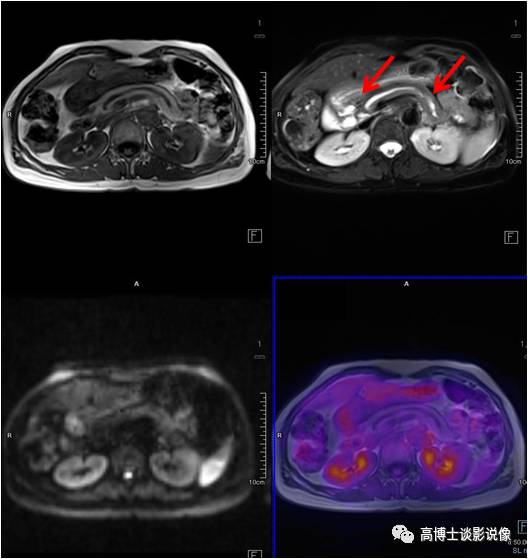

膀胱癌

老年男性,排尿中断半年余,无血尿。膀胱左后壁局限性增厚,病灶以宽基底与膀胱壁相连,长径约1.8cm。膀胱镜证实为膀胱癌。

点评

膀胱癌是泌尿系统最常见的恶性肿瘤,较为明确的两大致病危险因素是吸烟和职业接触芳香胺类物质。绝大多数的膀胱癌患者最初的临床表现是血尿。本例患者无血尿症状,经PET/MR检查偶然发现了膀胱内占位病变。

结肠癌

老年男性,不明原因贫血,伴下腹痛。乙状结肠肠壁明显增厚伴肠腔狭窄,FDG呈高代谢,肠镜病理证实为乙状结肠癌。

结肠癌早期可以没有任何症状,中晚期可表现为腹胀、消化不良,而后出现排便习惯改变和便血。肠镜是筛查的最佳手段。此例患者检查发现肠壁增厚,FDG代谢增高,提示肠癌可能性大,PET/MRI可以帮助做手术前的评估,分期,决定治疗方案。